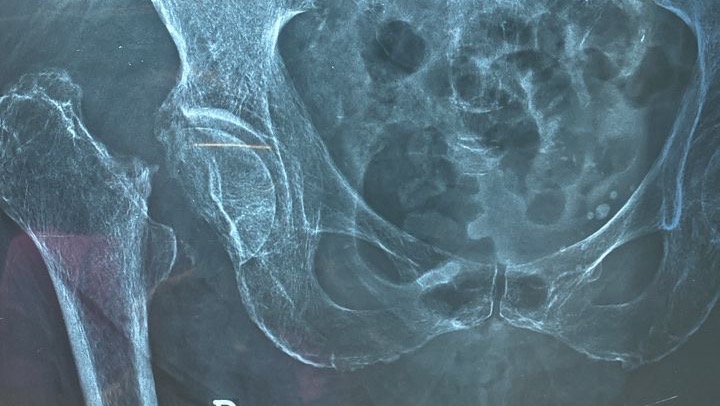

Recientemente sufrió una fractura de fémur, lo que ha limitado completamente su movilidad y le ha generado un dolor constante. El diagnóstico médico es claro: necesita una operación urgente para colocar una prótesis de reemplazo articular. Esta cirugía es fundamental para que pueda volver a caminar, aliviar el dolor y mejorar significativamente su calidad de vida.